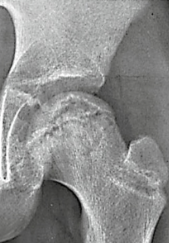

What stage of Perthes disease is this image?

Stage 1

Stage 2

Stage 3

Stage 4

A

Stage 4: reossification